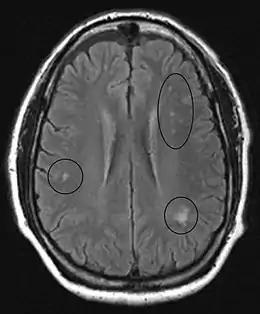

MRI image of the brain in vitamin B12 deficiency, axial view showing the "precontrast FLAIR image": note the abnormal lesions (circled) in the periventricular area suggesting white matter pathology.

MRI of the brain may show periventricular white matter abnormalities. MRI of the spinal cord may show linear hyperintensity in the posterior portion of the cervical tract of the spinal cord, with selective involvement of the posterior columns.